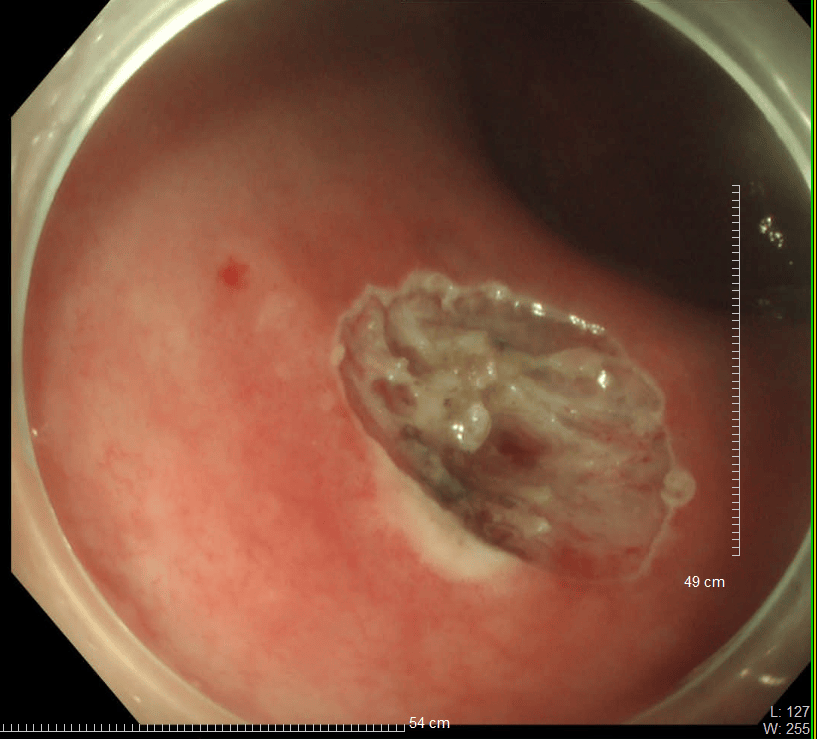

36歲的王先生在蘇州高新區人民醫院行胃腸鏡檢查時,發現直腸裡有1個息肉和2個黏膜下半球型隆起,表面光滑、顏色發黃,大小直徑約1.0cm,當時便做了超聲內鏡檢查,顯示2個隆起的腫物位於直腸黏膜下層,可能是神經內分泌腫瘤,1個粘膜層隆起的息肉可能是腺瘤腫瘤。消化科團隊立即為王先生進行了腸鏡下黏膜剝離術切除了2個粘膜下腫物,同時進行了腸鏡下粘膜切除術解決了1個腺瘤樣息肉,術後病理顯示:2個是神經內分泌瘤NET G1,切緣乾淨。1個管狀腺瘤伴低階別上皮內瘤變(屬於癌前病變),目前王先生恢復良好,已順利出院。

直腸神經內分泌瘤內鏡下治療的適應證包括腫瘤直徑<1 cm,侷限於黏膜或黏膜下層(T1期)的G1/G2級病變腫瘤。對直徑1-2cm的腫瘤,兼顧根治及功能保全,透過內鏡及影像學充分評估後選擇治療方式。內鏡下黏膜剝離術(ESD)是一項先進的內鏡下四級微創技術,醫生透過電刀,在內鏡下實現對胃腸道表淺病變的治癒性切除。

優勢在於該手術在避免外科手術的創傷、保留器官功能的同時,對病灶進行切緣陰性的整塊切除,具有手術創傷小,時間短,費用低,併發症少,恢復快,預後好等特點腫瘤